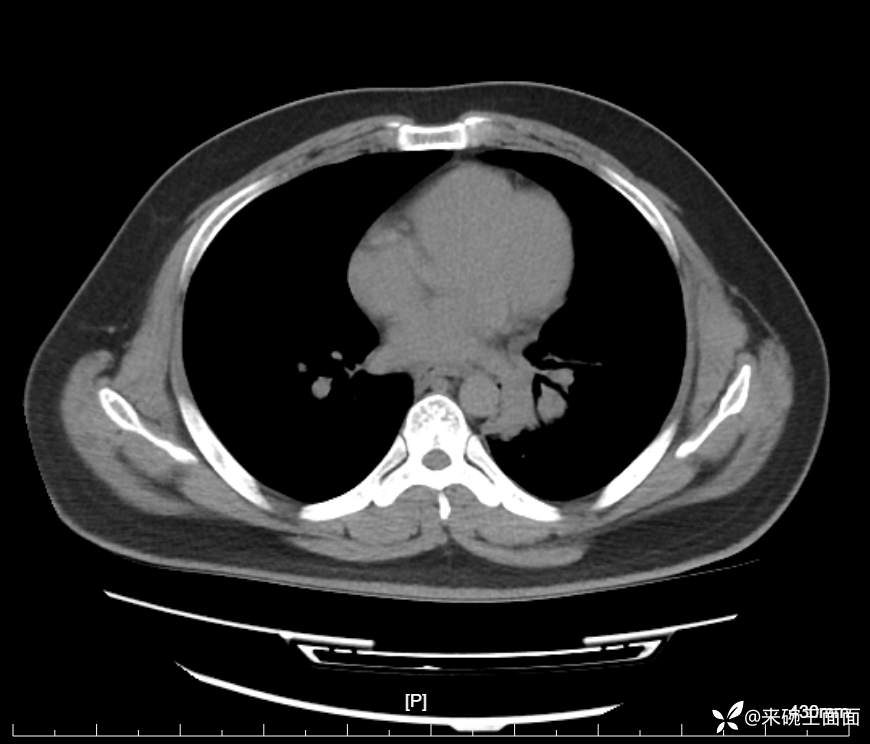

性别:男

年龄:27岁

主诉:胸闷胸痛数月余,休息后可自行缓解,无咯血症状。

个人史:数年吸烟史,具体不详。